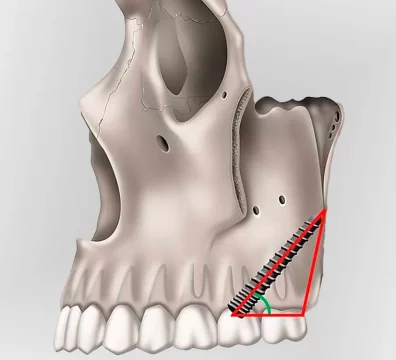

Los implantes pterigoideos son implantes dentales largos que se colocan en la apófisis pterigoidea , una zona ósea profunda y muy densa situada en la parte posterior del maxilar superior. Esta región ofrece una excelente estabilidad primaria , incluso en pacientes con gran pérdida ósea.

A diferencia de los implantes tradicionales, los implantes pterigoideos se colocan con una inclinación específica , anclándose en hueso de alta calidad y permitiendo la colocación de prótesis fijas sin necesidad de regeneración ósea previa.

Implantes pterigoideos : se anclan en la zona pterigoidea del maxilar